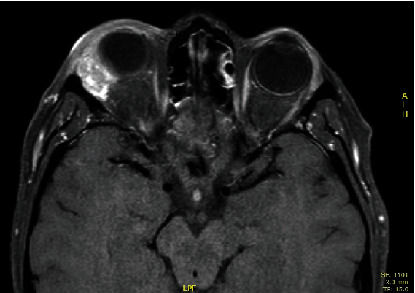

背景:泪腺上皮性肿瘤非常罕见,泪腺原发性导管腺癌仅占所有泪腺上皮性肿瘤的 2%。考虑到其罕见性和缺乏统一的诊断标准,治疗方案也没有得到很好的界定。在本研究中,我们描述了一例 Her-2 阳性病例,并回顾了之前报道的病例。研究方法2012年,一名42岁的女性患泪腺原发性导管腺癌,她接受了经眼球前眶切除术和辅助放疗。2013 年 7 月,她出现局部复发,于是接受了眼眶外扩张术。2013年11月,因颈部结节进展,她接受了7个周期的化疗(顺铂和表柔比星),同时使用人源化单克隆抗体靶向HER 2疗法(曲妥珠单抗和百妥珠单抗),取得了明显的反应率。随后,她接受了腮腺全切除术和右颈部淋巴结切除术,并接受了辅助性甲状腺治疗。结果:治疗结束九年后(113 个月),患者无病存活,毒性反应可接受。结论对于泪腺原发性导管腺癌,考虑到其往往具有侵袭性,早期诊断和多模式治疗至关重要。考虑到缺乏治疗指南,病例报告记录有助于患者的管理。

Background: Epithelial tumors of lacrimal glands are rare and primary ductal adenocarcinoma of the lacrimal gland accounts for only 2% of all epithelial lacrimal gland tumors. Considering its rarity and lack of uniform diagnostic criteria, treatment protocols are not well defined. In this study, we describe a Her-2 positive case and review previously reported cases. Methods: In 2012, a 42-year-old woman affected by primary ductal adenocarcinoma of the lacrimal gland was treated with transpalpebral anterior orbitotomy and adjuvant radiotherapy. In July 2013, she presented local relapse and she underwent orbital exenteration. In November 2013, for neck nodal progression, seven cycles of chemotherapy (cisplatin and epirubicin) associated with a humanized monoclonal antibody-targeting HER 2 therapy (trastuzumab and pertuzumab) were performed, with a marked response rate. Then, she underwent total parotidectomy with right neck lymphadenectomy and adjuvant hadrontherapy. Results: Nine years later (113 months) after treatment completion, the patient was alive without disease and with acceptable toxicity. Conclusions: In primary ductal adenocarcinoma of the lacrimal gland, early diagnosis and multimodal treatments could be crucial, considering its often aggressive tendency. Considering the lack of treatment guidelines, case report recording can be useful in patient management.